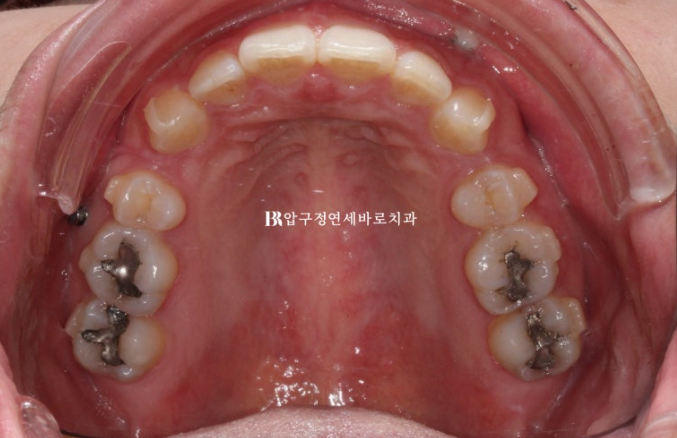

22.09~24.12

유지장치까지 들어간 모습입니다.

발치 공간으로 어금니 쓰러짐 없이 뿌리까지 평행하게 이동 된 것이 확인됩니다.